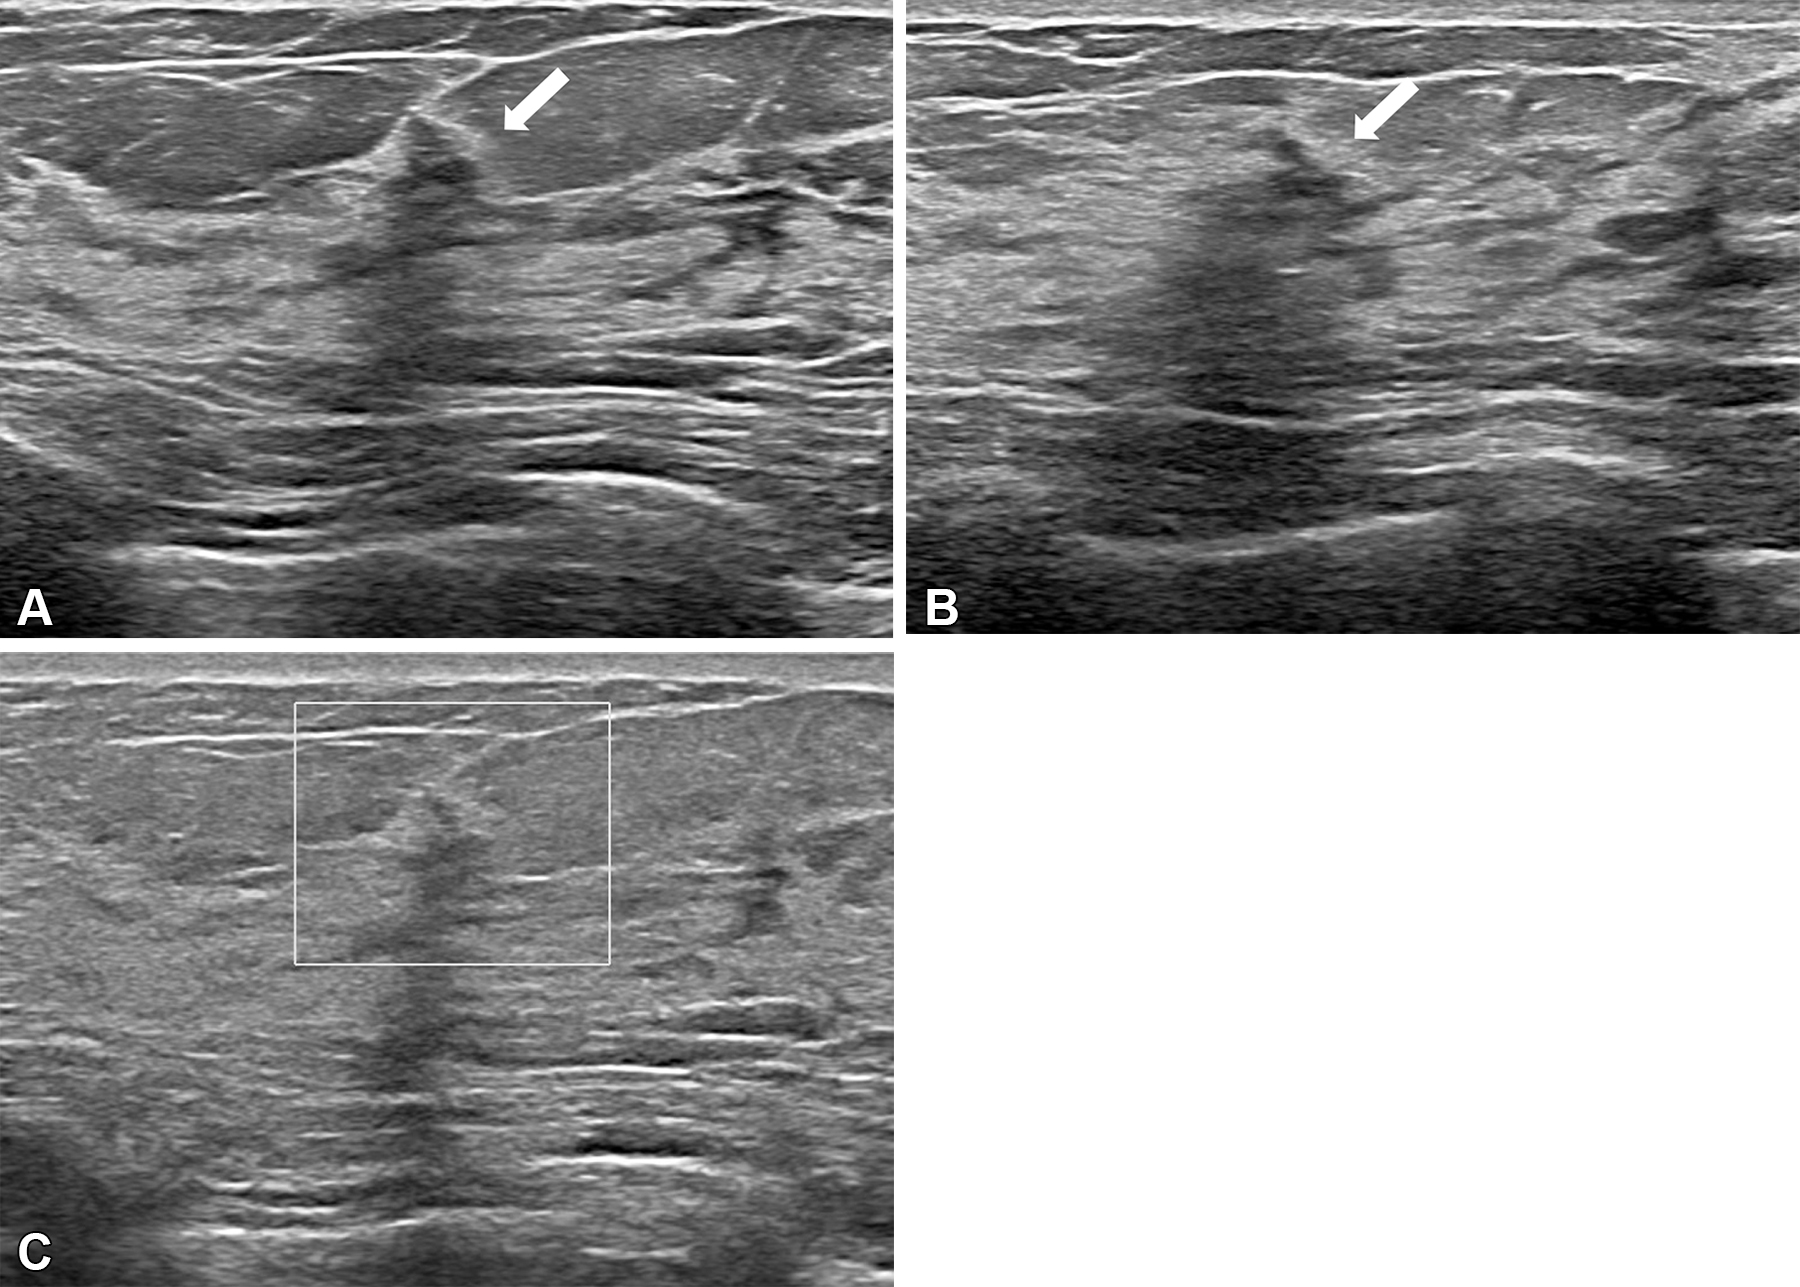

While ultrasound is frequently used, its performance varies depending on operator skill and it has typically demonstrated poor repeatability. Mammography's performance suffers when imaging dense breast tissue, and MRI has shown it can both under- and overestimate residual disease (and MRI is expensive and cannot be used on patients who are allergic to contrast agents or have metal implants). However, ABVS is a new technique that covers the whole breast using an automated ultrasound system at frequencies of 5 to 15 MHz.

Peng and colleagues investigated the performance of ABVS for assessing residual breast tumor size after neoadjuvant therapy, comparing it to hand-held ultrasonography, mammography, and MRI.